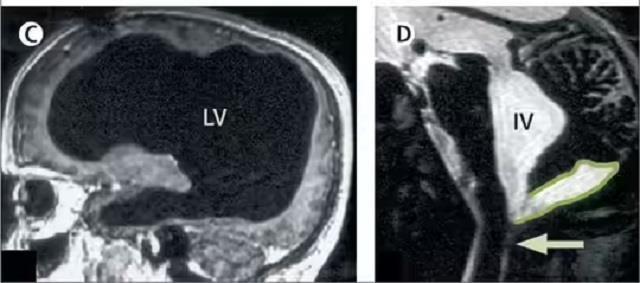

‘द लैंसेट’ में प्रकाशित इस केस रिपोर्ट के अनुसार, उस व्यक्ति के सिर में दिमाग की जगह तरल पदार्थ भरा हुआ था, और केवल एक पतली परत में ब्रेन टिश्यू बचा था। इसे हाइड्रोसेफेलस नामक स्थिति कहा जाता है, जिसमें दिमाग के अंदर तरल पदार्थ (cerebrospinal fluid) जमा हो जाता है।

रिपोर्ट के अनुसार, जब वह व्यक्ति सिर्फ 6 महीने का था, तब उसे पोस्टनैटल हाइड्रोसेफेलस हुआ था, जिसके इलाज के लिए उसके सिर में शंट सर्जरी की गई थी। 14 साल की उम्र में भी उसे पैर में कमजोरी और चलने में परेशानी महसूस हुई थी, लेकिन इलाज के बाद वह पूरी तरह ठीक हो गया। बाद में 44 साल की उम्र में दोबारा पैर में कमजोरी आने पर उसका CT और MRI स्कैन किया गया, और तब पता चला कि उसका लगभग पूरा दिमाग तरल पदार्थ से भरा हुआ है।